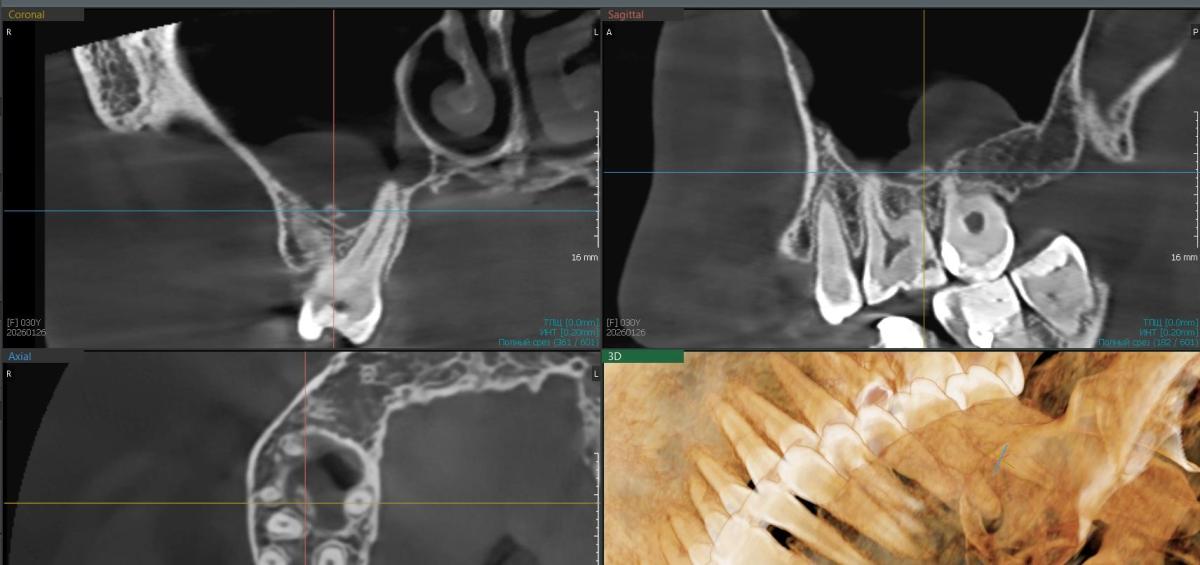

Недавно сделала кт челюстей и заметила какой-то кусочек в пазухе. Как будто кусок зуба. Может ли болеть из-за него? У меня сохранены как сувениры все удаленные зубы, я посмотрела и у одного из них как раз на корешке скол.

Если я права, куда мне идти с этой проблемой и как ее решать? Очень страдаю, помогите ;(. Боль терпимая, но не снимается обезболками, из-за этих болей не заметила у себя два пульпита на этой же стороне.